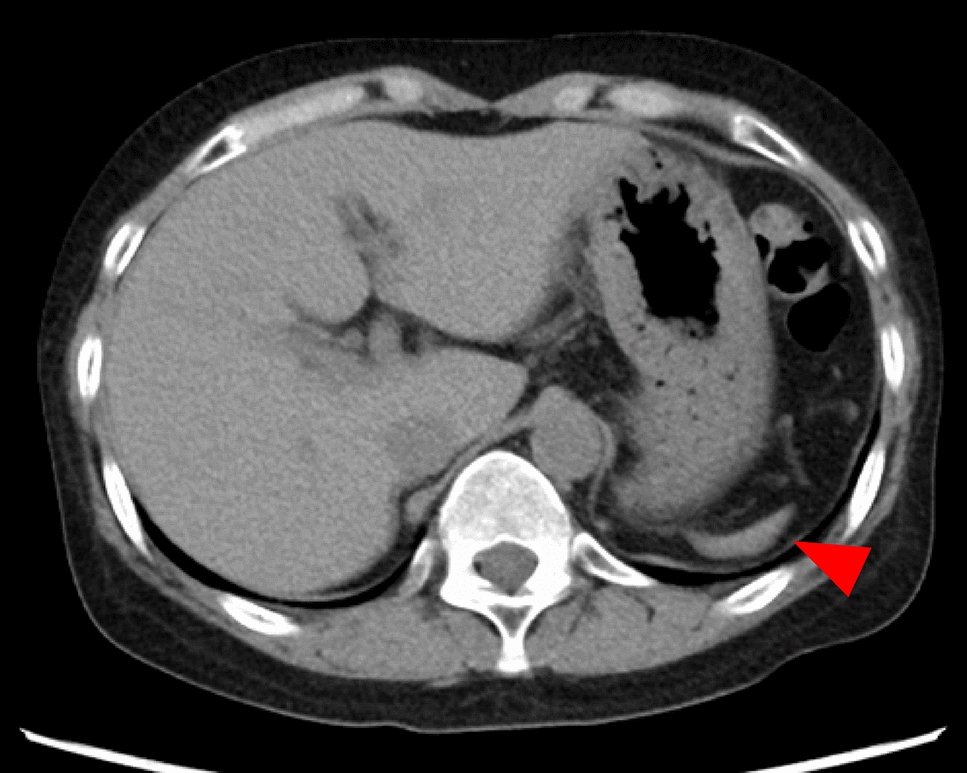

Overall, 95 patients with HJBs who had not undergone splenectomy were included in this study. A representative peripheral blood smear demonstrating the presence of HJBs is shown in Fig. 1. The median age was 66 years (range, 16–95), with 68 (72%) being male. The median spleen volume was 34 mL (range, 1.2–410 mL), while the median ideal spleen volume was 210 mL (range, 110–320 mL). A representative CT image of a patient with marked splenic atrophy (measured volume, 5.9 mL) is shown in Fig. 2. In most cases, the measured spleen volume was smaller than the ideal spleen volume, with a median relative difference of –82% (range, –99 to 97%) (Fig. 3).

Fig. 2

Abdominal CT image of a representative patient demonstrating marked splenic atrophy (red arrow). The measured splenic volume was 5.9 mL. CT computed tomography